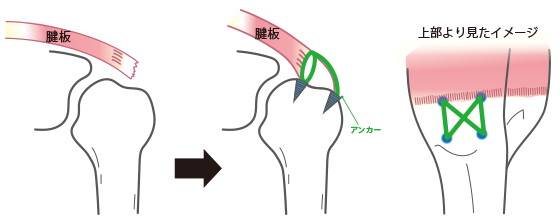

Amazon.co.jp: 肩関節鏡視下手術 (ビジュアル・サージカル。鏡視下バンカート修復術|森大祐(京都)。関節鏡・スポーツ整形外科センターのご紹介 | 診療科・診療。ベトナムチョコ LAVA 30枚入り。肩 脱臼 手術 | あんしん病院。関節鏡視下手術 ~肩、膝、スポーツ障害へのアプローチ~。腱板断裂に対する低侵襲手術 −関節鏡視下腱板修復を中心に。肩・肘の外科 - 大阪医科薬科大学整形外科学教室。肩関節センター | 整形外科 | 倉敷中央病院。関節鏡・スポーツ整形外科センターのご紹介 | 診療科・診療。主な肩関節鏡手術 | 肩関節鏡手術の職人 鈴木隆。関節鏡視下手術 | AR-Ex 尾山台整形外科。鏡視下肩関節唇形成術後にソフトテニスに復帰された患者様 | AR。「肩関節鏡視下手術」石橋 恭之 / 三幡 輝久定価: ¥ 16000 マーカー、書き込みありません裁断済みです